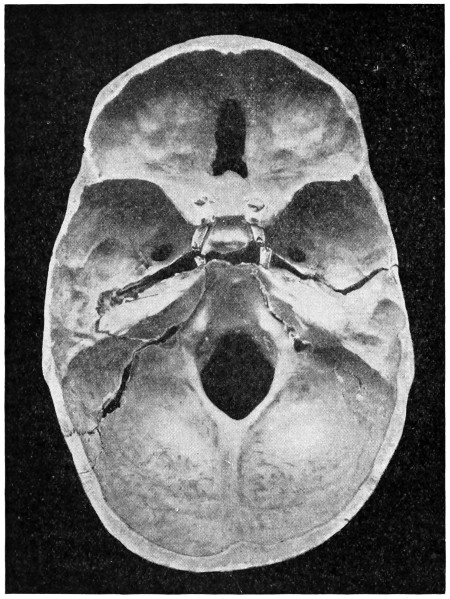

50 A and B. The inner aspect of the skull and the same seen on transillumination 137

51. To illustrate compression of the brain as produced by an extra-dural hæmorrhage from the middle meningeal artery[x] 141